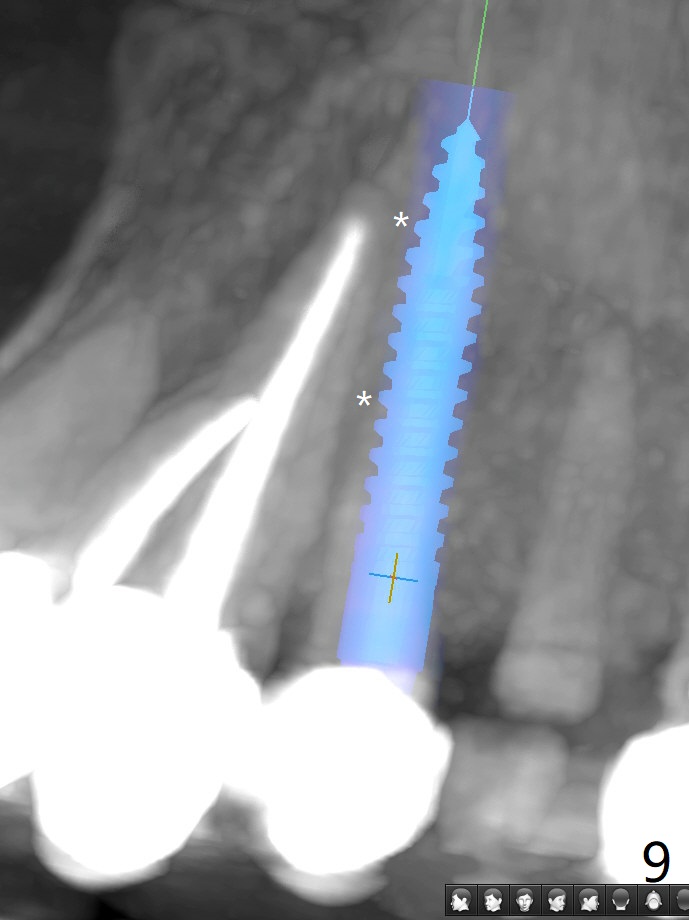

68岁女左上4颊侧瘘道(图一:*),与根尖颊侧骨板缺失相通,其实腭侧根尖周围病变更大(也与颊侧窝相通),术中没有注意腭侧根接近3(图二:P),稀里糊涂的基本顺着腭侧根(颊侧)走向钻洞(图四,与图三理想方向对比),突然记起术前设计钻洞必须在腭侧牙槽窝远中颊侧,在远中建立新洞眼(图五),之后无法再次建立新洞眼,只好利用同一个侧面切割钻头将钻洞往远中移位,同样效果不佳(图六),最后只好放弃,放置粘性骨粉(图七:*),覆盖PRF膜,6个月胶原膜,PGA缝线,牙周胶水。术后重新分析表明顺着腭侧牙槽窝种植与尖牙还是有分离(图八,九:*),因为牙槽窝是斜型的(图十:黑色),不过离颊侧骨板也接近(图八:B)。所以钻洞必须斜型针对远中骨壁,表浅些(图十一:红色箭头);一旦进入骨板,改变角度(图十二:红色箭头),适当矫枉过正,随着植体增大,钻洞会往近中偏移(白色箭头)。最好植体方向理想(图十三)。不过植骨后钻洞偏移可能性比较少。缝线和牙周胶水似乎是一个稳妥固定胶原膜方法。术后病人抱怨水肿严重,术后八天颊侧根尖隆起是由于骨粉推出骨板之外(图十五,十六:*),上颌窦底板无意穿孔(^)伴有上颌窦膜(M)增厚,与术前对比(图十七:上颌窦窦腔清晰)。术后一个月6个月吸收膜不见了,大多数缝线已经脱落,最后两根缝线撤除后,牙槽窝开口已经关闭,好像主要成分是骨粉(图十八)。术后5个月牙槽嵴宽,角化龈也宽,好像可以植入4x11.5毫米植体(图十九)。